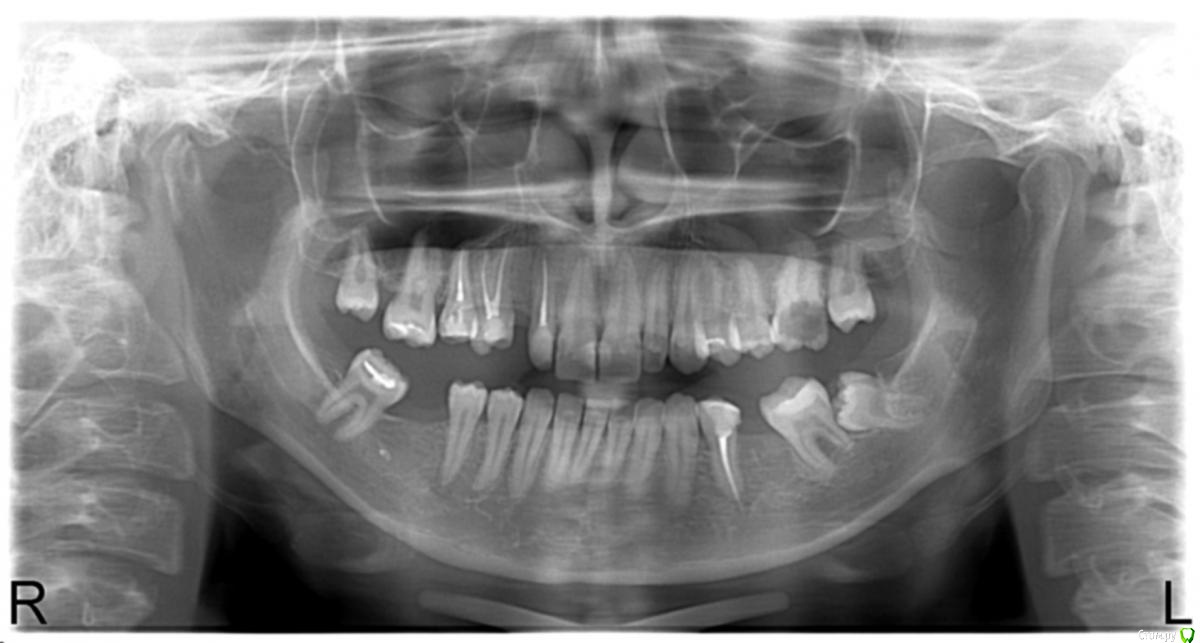

Добрый день! Посоветуйте пожалуйста, зубы необходимо лечить,перелечивать. Но так как стремлюсь к красивой улыбке,что лучше сделать? ставить импланты или коронки. Пока была только в одной клинике, они ужасались зубами, но сказали если я буду ходить каждый день они мне вылечат все быстро, недели за 2 максимум. И предлагали ставить почти на все зубы коронки. Почему-то меня это смущает, спиливать почти все зубы(в том числе и здоровые) боязно... Сейчас сделают красиво,а лет через 5-10 мне что делать... Возможно я и ошибаюсь, прошу квалифицированной помощи. Снимок прилагаю.

Если судить только по вашему снимку:

1. Удаление 3.8 (мудрый зуб снизу слева) и возможно 2.6

2.Ортодонтическое лечение

3. Имплантация

4. Протезирование 1.5 1.4 1.2 3.4 и имплантов